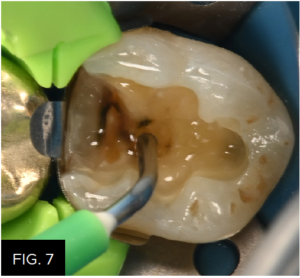

With such a large preparation, using a bulk fill composite will increase the technique’s efficiency. First, as a means to wet the surface of the preparation to assist in the adaptation of the paste bulk fill composite, a very thin layer of Filtek™ One Flowable Bulk Fill (3M) was applied to the entire preparation and is not light cured. (FIG. 7)